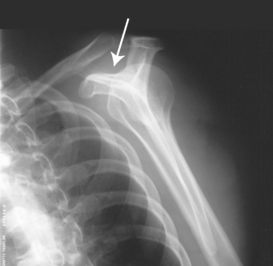

Fig. 5-14 A, AP shoulder, external rotation humerus: greater tubercle in profile (arrow). B, AP shoulder, neutral rotation humerus: greater tubercle (arrow).

External rotation: The greater tubercle of the humerus and the site of insertion of the supraspinatus tendon are visualized (see Fig. 5-14, A).

Neutral rotation: The posterior part of the supraspinatus insertion, which sometimes profiles small calcific deposits not otherwise visualized (see Fig. 5-14, B), is seen.